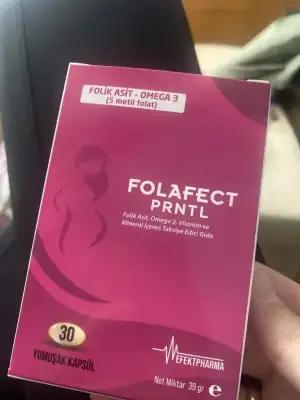

güle güle kullanın inşallah. keşke benim olsaBuarada annem sabah bimdeki küvetten falan almış. Ya bu annaneleri biri durdursunEki Görüntüle 3239771